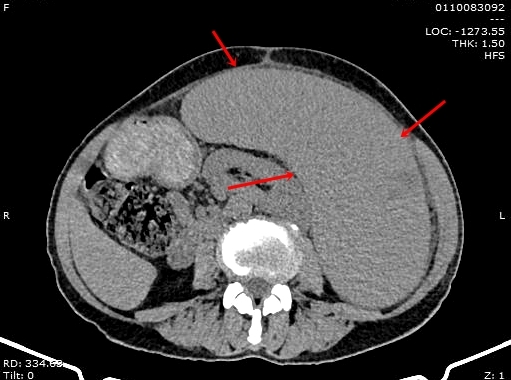

Hình ảnh chụp cắt lớp lá lách kích thước “khủng” chiếm hơn nửa ổ bụng của bệnh nhân H.

Kết quả chụp cắt lớp vi tính cho thấy hình ảnh lá lách rất to, kích thước 21 x 30 cm, chiếm nửa ổ bụng, kéo dài đến hố chậu, một phần lách bị nhồi máu do tắc mạch. Các bác sĩ chẩn đoán bệnh nhân bị lách to độ IV, nhồi máu lách trên bệnh nhân rối loạn sinh tuỷ, cần thực hiện phẫu thuật cấp cứu cắt lách để tránh nguy cơ hoại tử và vỡ lách gây mất máu cấp dẫn đến tử vong cao.